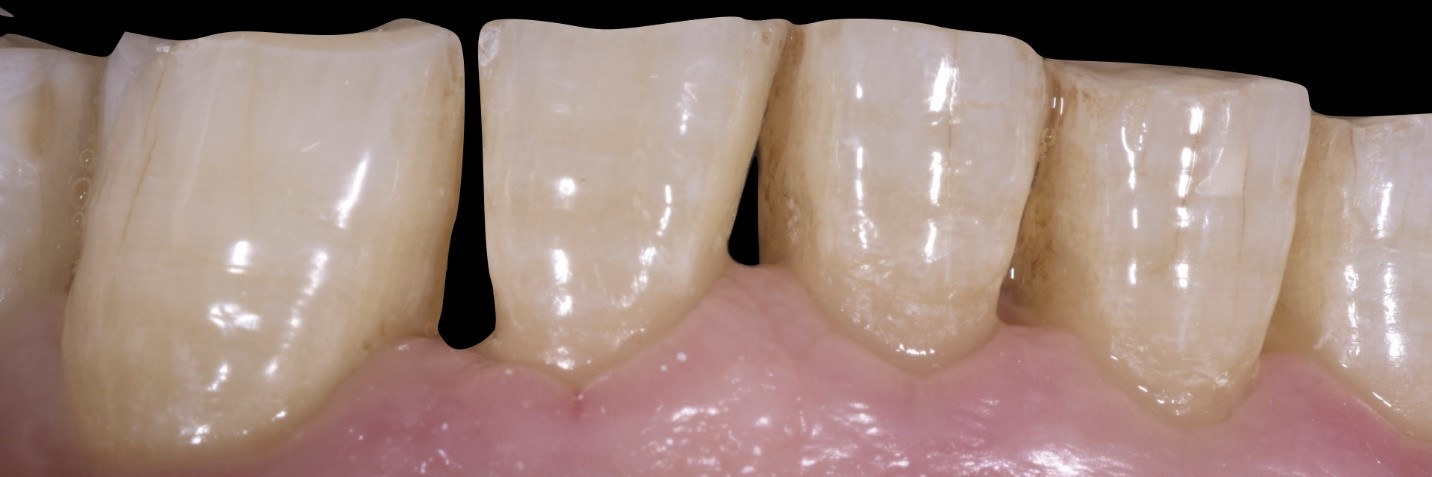

Fig. 6

Si noti il grado di apertura dentale interprossimale che determinerà un migliore alloggiamento del restauro ceramico all’atto della cementazione, nonché un’agevole impronta, ottica o tradizionale.